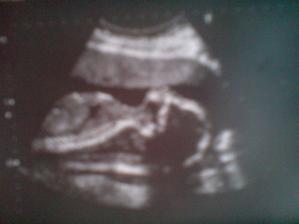

23.5. Ultrazvuk v 21.týdnu-miminko má všechno co má mít a je nádherný a zdravoučký:o)